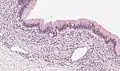

| Micrograph showing a mucinous cystadenoma of the ovary. H&E stain. | |

Mucinous cystadenoma is a benign cystic tumor lined by a mucinous epithelium. It is a type of cystic adenoma (cystadenoma).

PRMC and benign mucinous cystadenoma of the ovary are microscopically similar. Both are multiloculated cystic neoplasms and are lined by a single layer of tall columnar cells with a clear basal nucleus and cytoplasm. Both of them have identical histochemical and ultrastructural features.[9] Flat to low cuboidal cells, resembling mesothelial cells, in the lining interspersed between columnar cells in the same area is the only histological difference between the two tumors.[9]